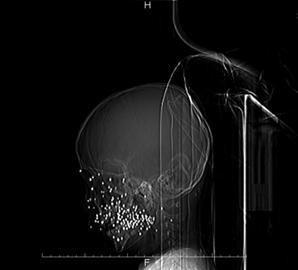

至九院时,男孩受伤已超过8小时。经过诊断,男孩面部近距离被“霰弹枪”击伤,导致面部上颌窦开放伤,右侧面部上颌窦全部被打穿,右侧面部皮肤和肌肉被全部破坏,上颌骨及下颌骨折并有骨组织缺损,近百粒弹珠状碎片留在面部的软组织及骨骼内,且伴随有面部皮肤火器烧伤。

男童的创面之大、伤势之重让医生们感到震惊。医院随即全力抢救,综合五官科、口腔科、眼科整形外科等多科室医疗力量。手术持续6个多小时后,从患儿面部取出90多颗弹珠。患儿右侧上下牙槽骨全部破坏,另有大量碎片。面部皮肤要待创面清洁后二期缝合。